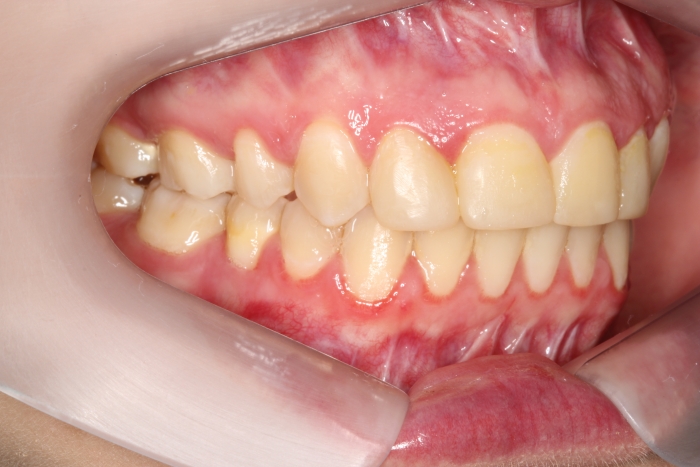

Mordida inicial